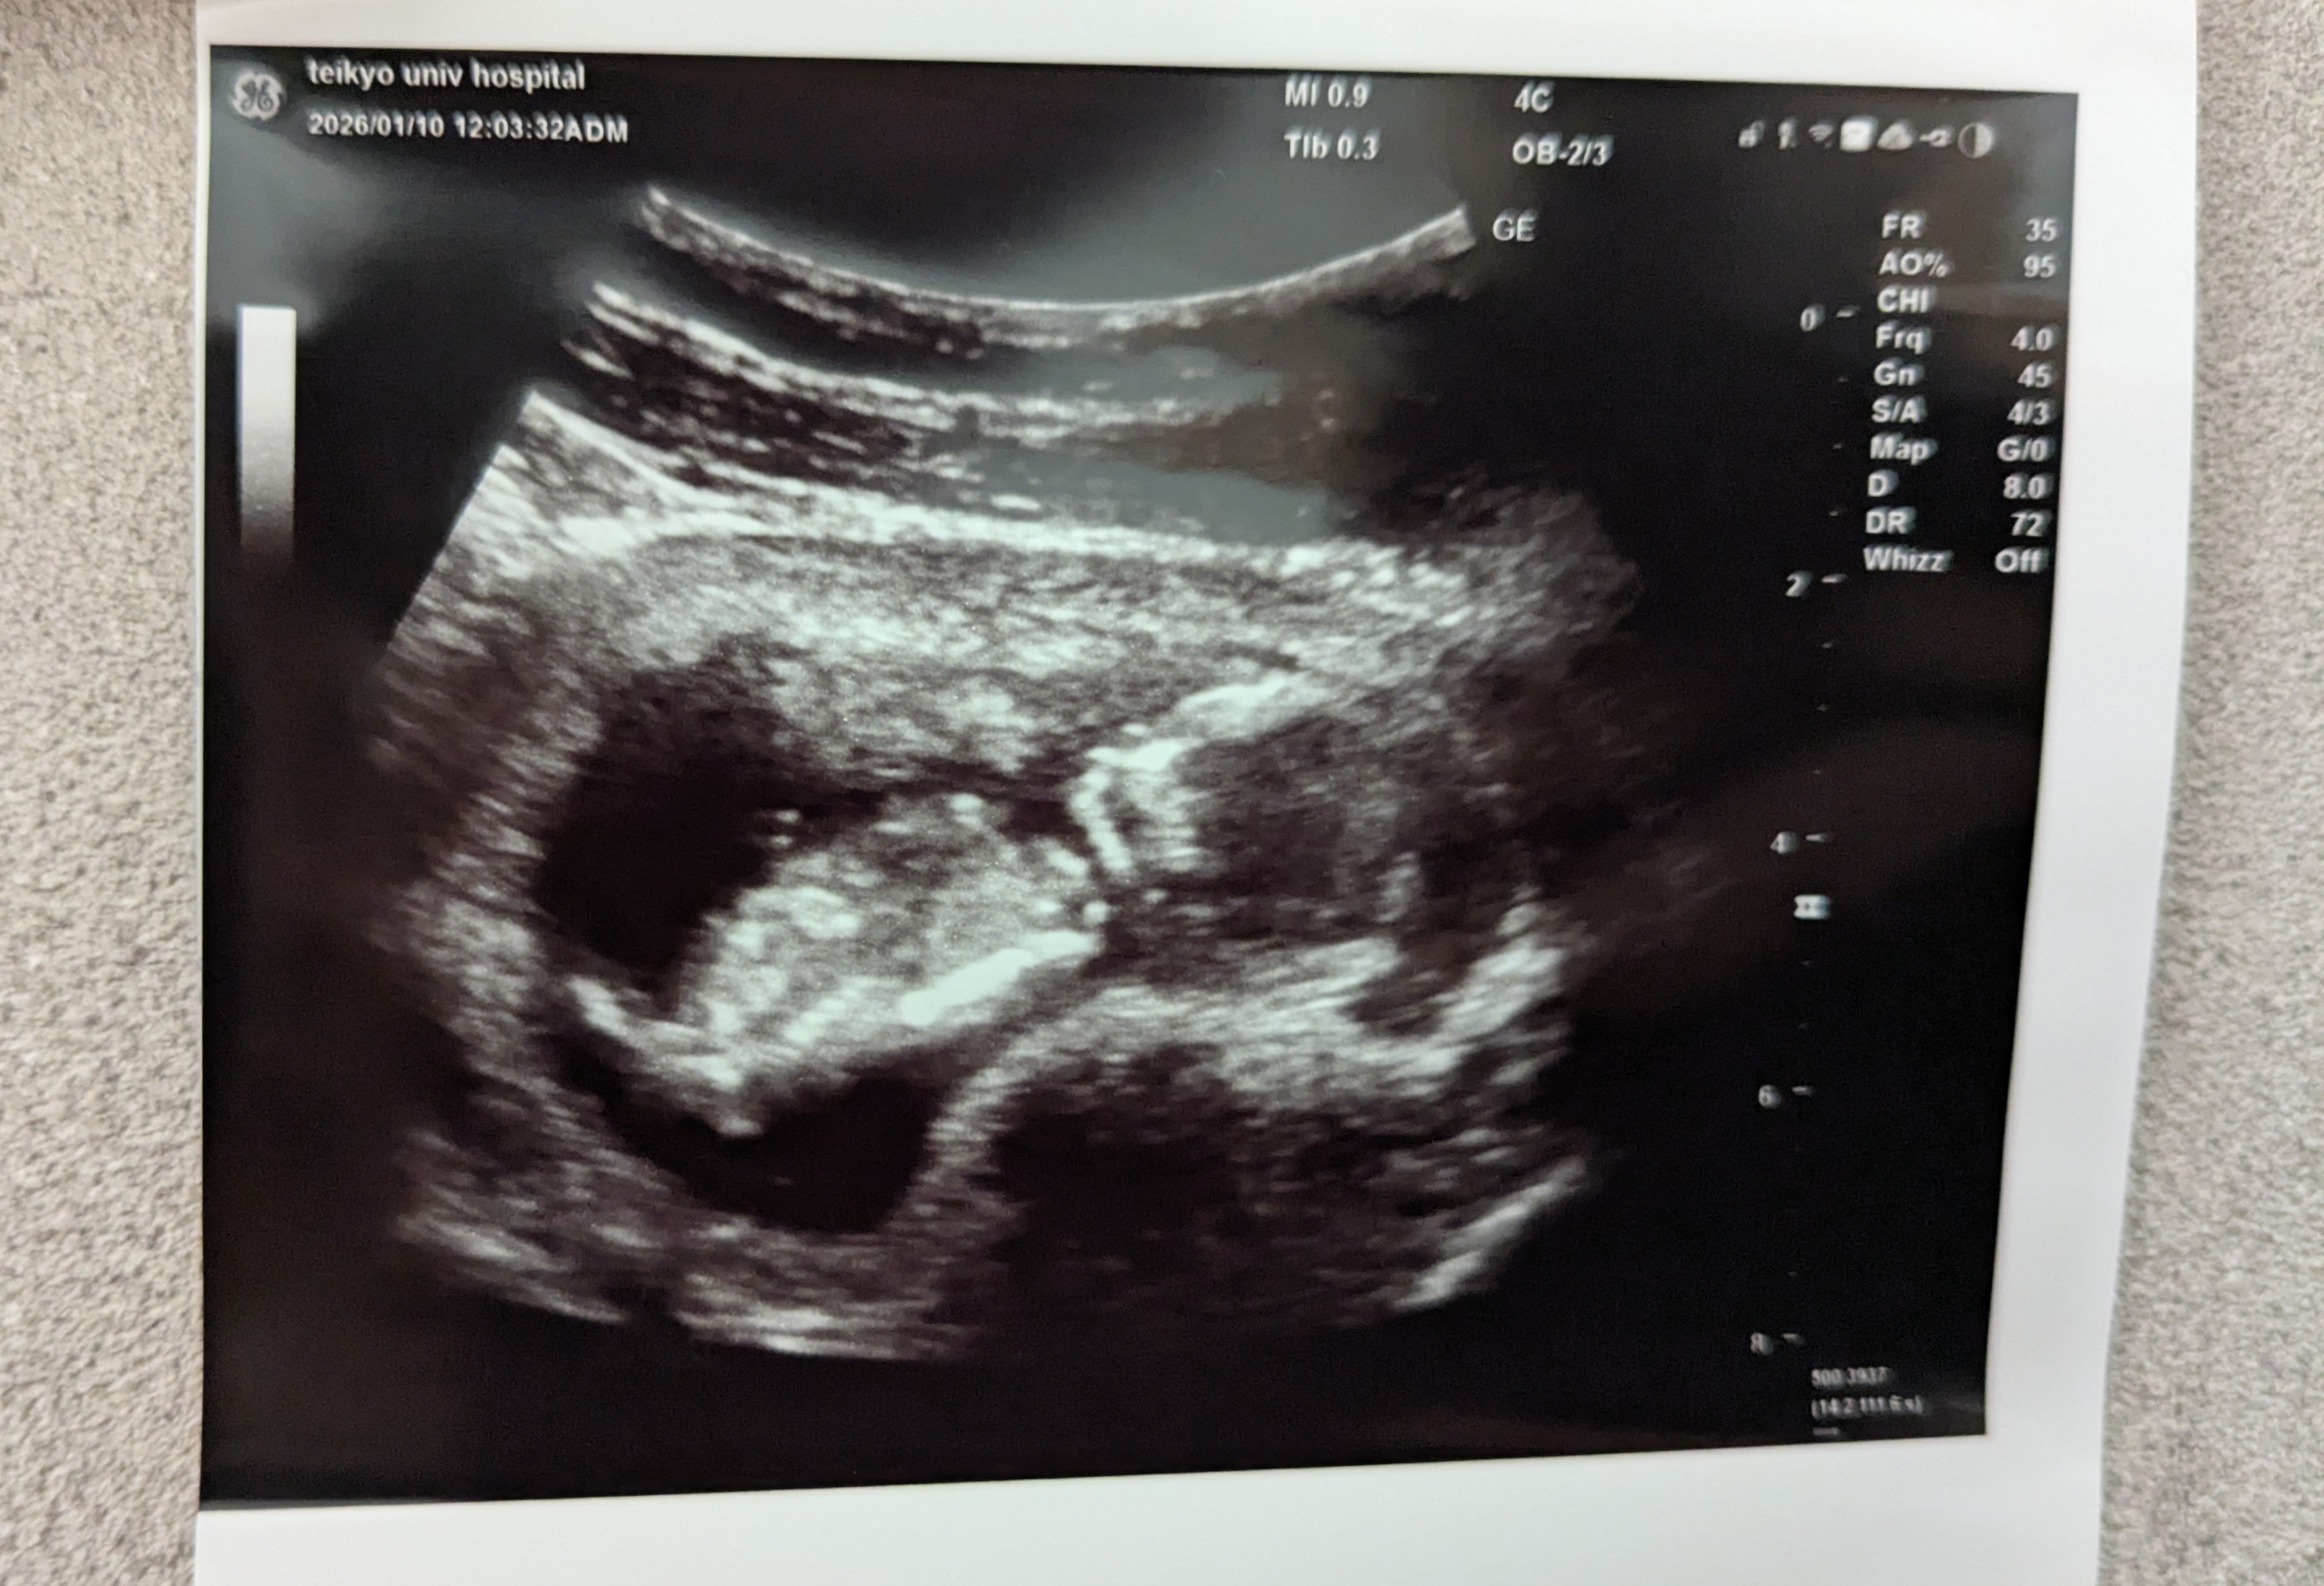

そして、今日は大学病院で「NIPT」を実施する日。

NIPTとは遺伝子を使った出生前診断のこと。

ダウン症等の遺伝子異常を事前に検知できるもの。

ただし、保険適用外で費用は約15万円ほどかかる。

あと、実施時期は妊娠9~16週目に限られるという。

確度はダウン症については99%超で検知可能であり、また血液検査のみなので検査による流産リスクも無し。

検査結果が出るまではちょっぴり悶々するよね。

また、やには最終的にこの病院で出産予定のため、長らくお世話になるなぁ。